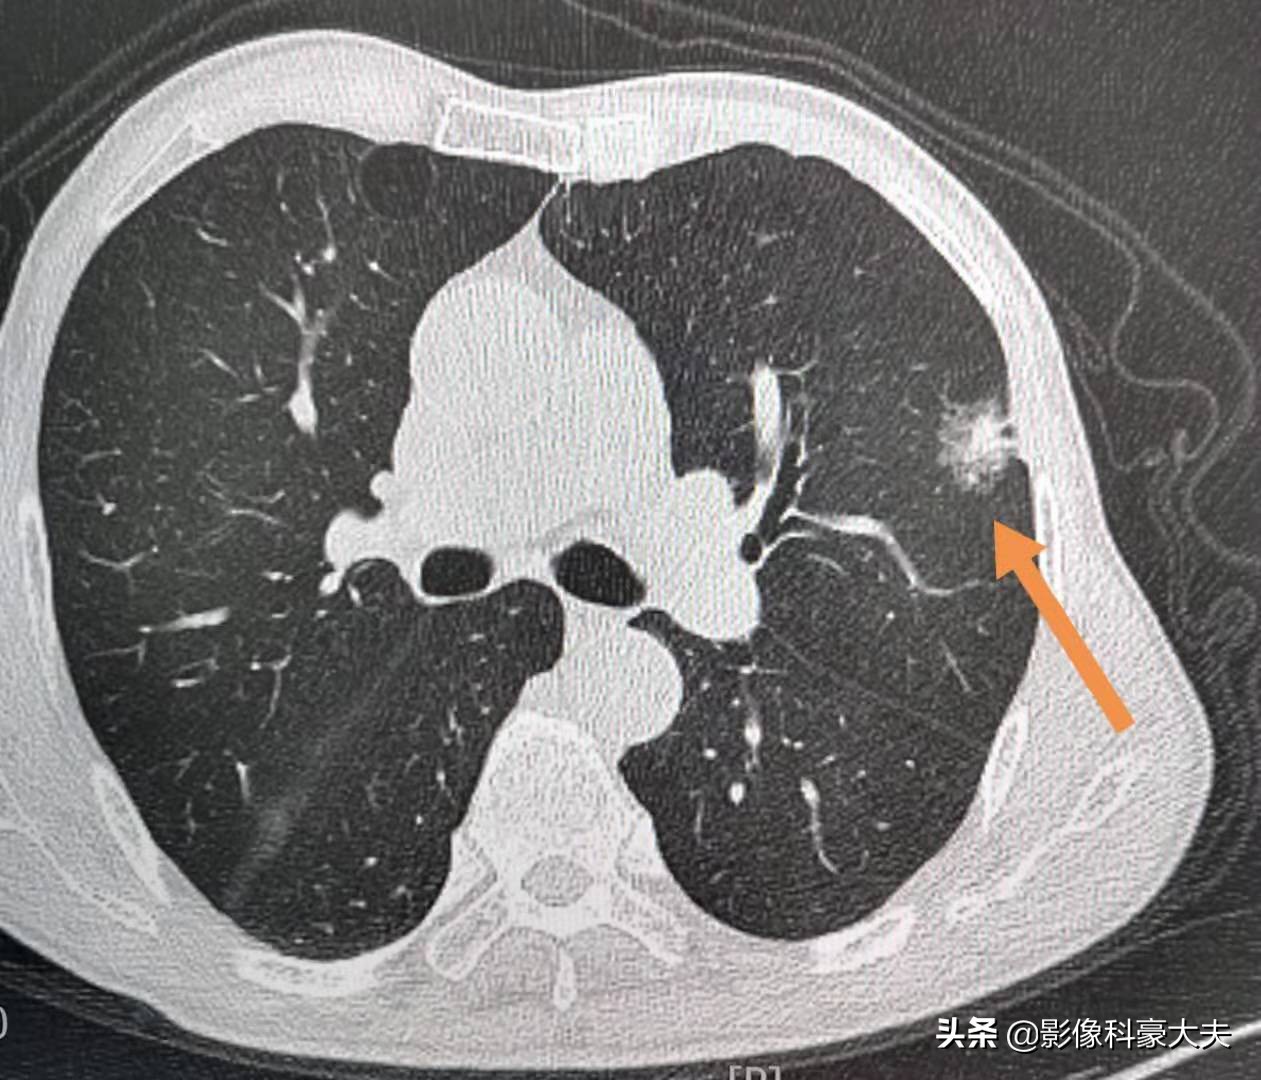

这位病人是因为冠心病、肩背部疼痛做全面检查,结果查出右上肺腺癌,比较幸运,将于近期手术治疗。

这是另一位老人,状况不好,因为左侧肩背部疼痛几个月,一开始吃点止痛药还有效,后来越来越重,影响到晚上睡眠,结果查了CT发现晚期肺癌。